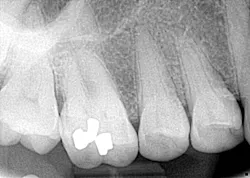

Clinical assessment revealed a 6 mm pink, raised, firm mass of osseous tissue measuring 12x12 mm. It was not tender to palpation and did not bleed easily when manipulated (figures 1 and 2). Radiographic assessment was within normal limits (figure 3).